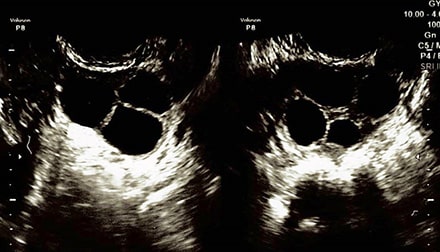

超音波検査

子宮(子宮筋腫、子宮腺筋症、子宮内膜ポリープ、子宮奇形等)や卵巣のう腫等、卵巣の異常の有無を見つけたり、卵胞や子宮内膜の計測をします。